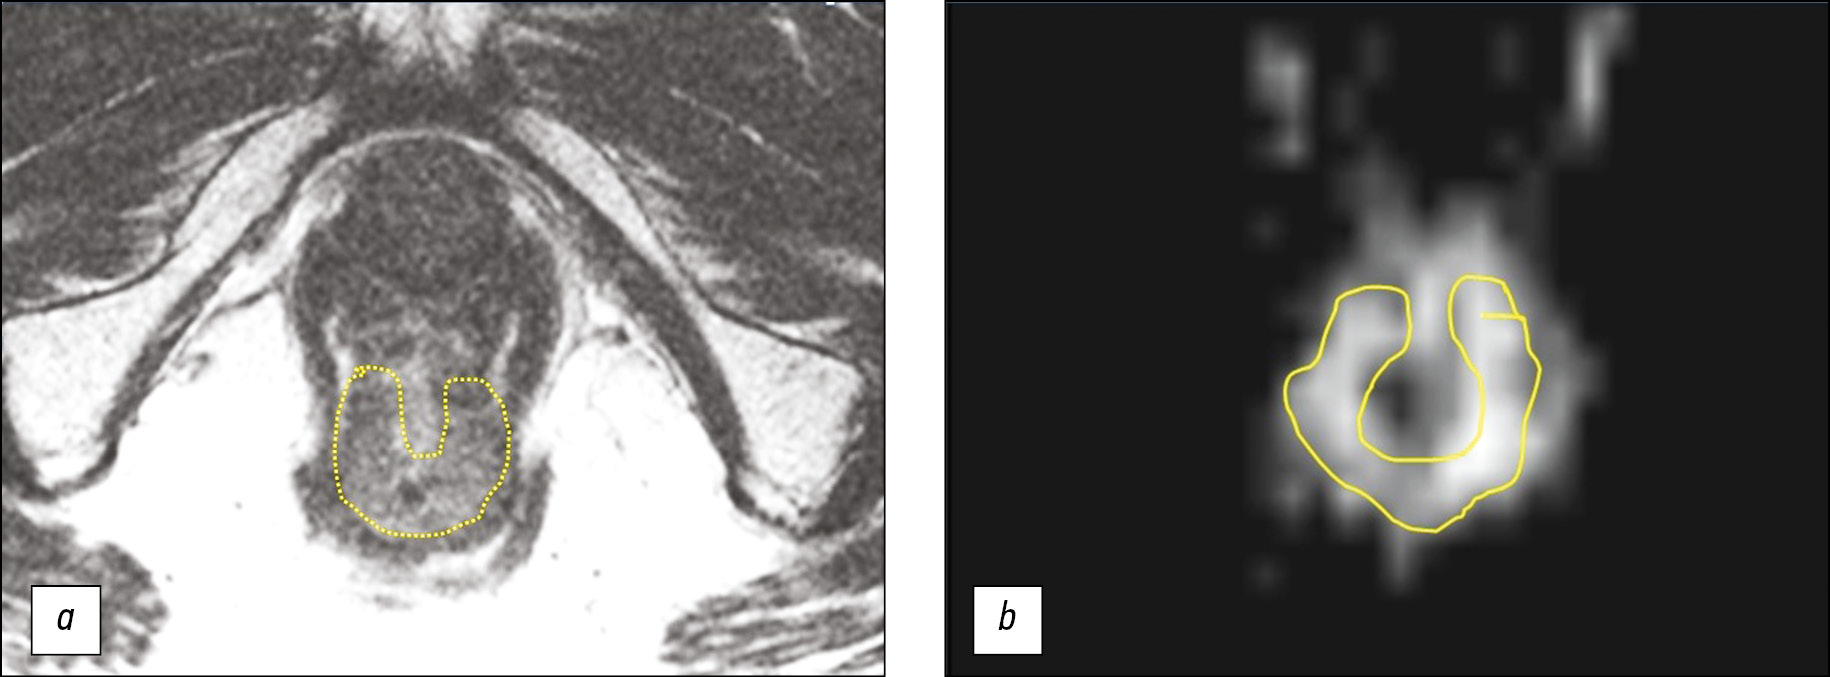

In the clinic of the A.F. Tsyba National Medical Research Radiological Center (Obninsk), a 73-year-old patient was followed up, diagnosed with C20 rectal cancer in accordance with ICD-10, cT3N0M0, and received NHRT (total focal dose of 50 Gy + capecitabine) and four cycles of consolidating polychemotherapy in accordance with the FOLFOX61 scheme. The pre-MRI treatment is presented in Fig. 1. At the end of neoadjuvant treatment, the set of control examination data (i.e., the MRI of the small pelvis, the endoscopic presentation of the tumor, and the results of digital rectal examination) indicated that the patient had a complete clinical response. A case follow-up was prescribed to and agreed upon by the patient.

Fig. 1. Magnetic resonance imaging of the tumor of the lower rectal ampulla before treatment, mrT3a: a ― T2-WI; b ― diffusion-weighted image. The tumor is encircled.